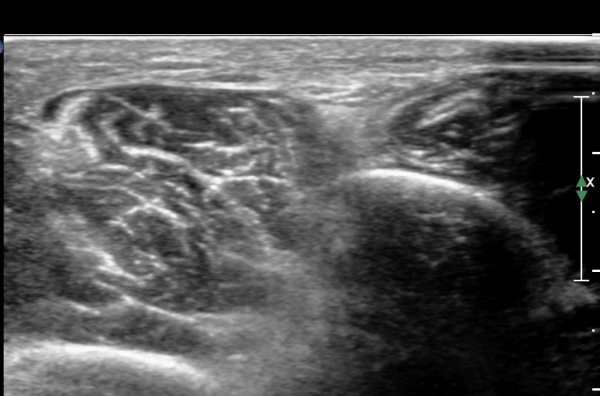

¾Æ·§´Ù¸® ¿ÜÃø Ⱦ´Ü¸é°Ë»ç¿¡¼ Àåºñ°ñ±Ù°ú ¹ß°¡¶ô½ÅÀü±Ù »çÀÌ¿¡¼ õºñ°ñ½Å°æÀÌ Á¤»óÀûÀ¸·Î °üÂûµÈ´Ù(»çÁø 1, , 2, 3, 4, 5).